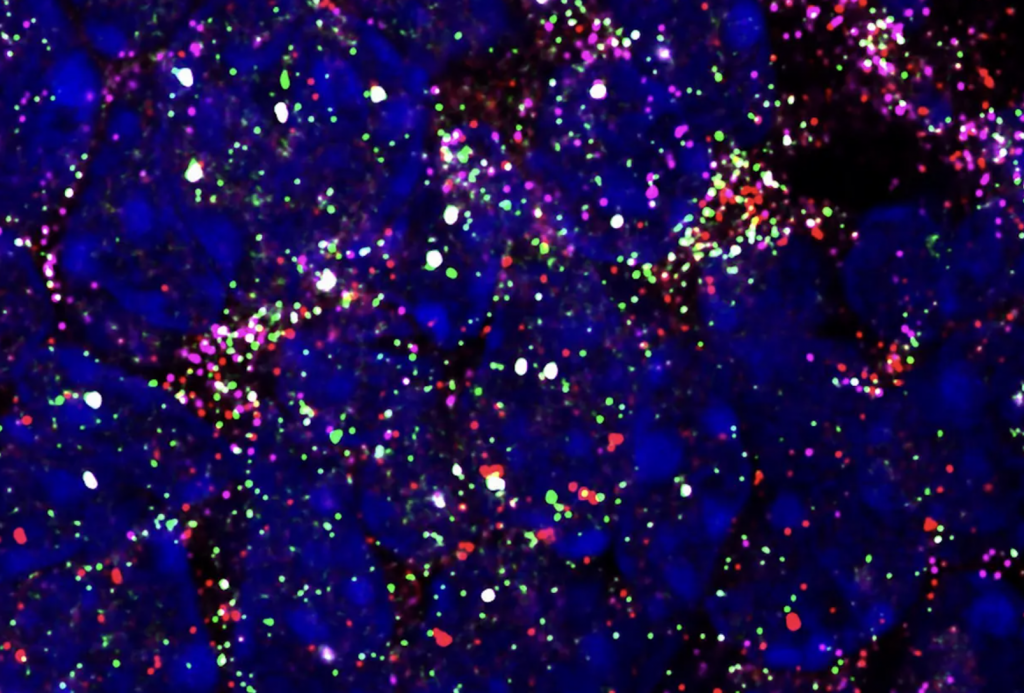

Building on this approach, such scientists are now increasingly turning to Fluorescence in situ hybridization or ‘FISH’ techniques, through which they attach colored markers to certain genes to lend them greater microscope visibility, but even though the method enables single molecular detection, it remains limited to identifying one gene at a time.

To get around this, Pixelbio has developed ‘HuluFISH,’ a flexible 3D printed biochip that allows clinicians to track a larger number of genes concurrently. Marketed as the ‘first individualizable multiplex smFISH solution,’ the firm effectively offers to produce the chips as a service, which allows clients to rapidly order from a selection of marked genes and receive the corresponding molecular devices for testing.

“[HuluFISH] will make the diagnosis of tumors or diseases easy and precise, and will change the way we diagnose and treat diseases in the long run,” concluded Liu. “We are confident that our probe can accelerate the development of drugs and vaccines by enabling the detection of SARS-CoV-2 and its receptor ACE2 mRNA at the single-cell molecule level.”